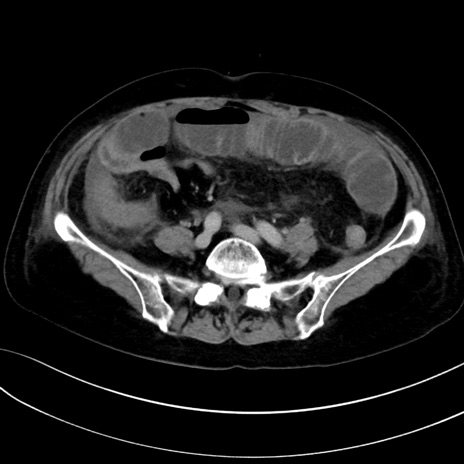

症例13 CT(横断像)1日半後